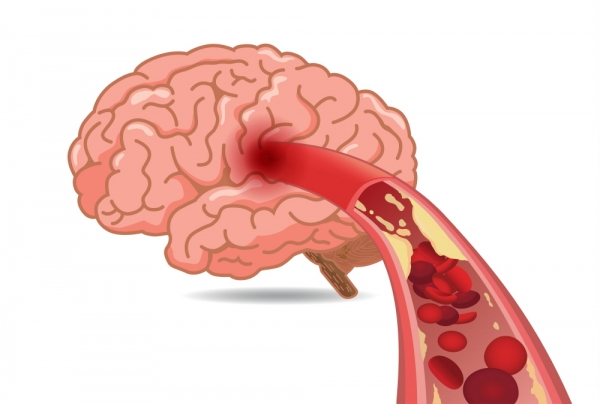

먼저 뇌경색이 무엇인지에 대해 쉽게 설명드리겠습니다. 뇌경색은 뇌로 가는 혈류가 차단되어 발생하는 질병으로, 일반적으로 뇌졸중이라고도 알려져 있습니다. 뇌혈관이 좁아지거나 막히면서 뇌가 필요한 산소와 영양분을 공급받지 못하게 되고, 이로 인해 뇌세포가 손상됩니다. 이러한 손상은 즉각적인 신체 기능 저하를 초래할 수 있으며, 심각한 경우 생명에 지장을 줄 수 있습니다.